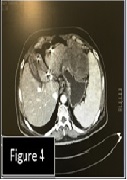

A Case Report Series of Renal Cell Carcinoma Patients Treated with Nivolumab and Radiotherapy

Francolini Giulio, Pezzulla Donato, Detti Beatrice*, Muntoni Cristina, Visani Luca, Topulli Juliana, Lo Russo Monica, Grassi Roberta, Becherini Carlotta, Livi Lorenzo